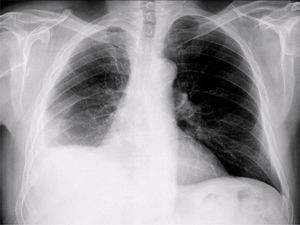

Presentamos el caso de un paciente de 63 años que consulta por disnea desde hace 15 días que se ha convertido a medianos esfuerzos desde hace unos meses. Exfumador de 10-15 cigarros al día hasta hace 20 años. Exposición laboral al amianto. Se efectúa radiografía de tórax urgente desde atención primaria con el siguiente resultado:

Radiografía de tórax anteroposterior (fig. 1): disminución de volumen del pulmón derecho.